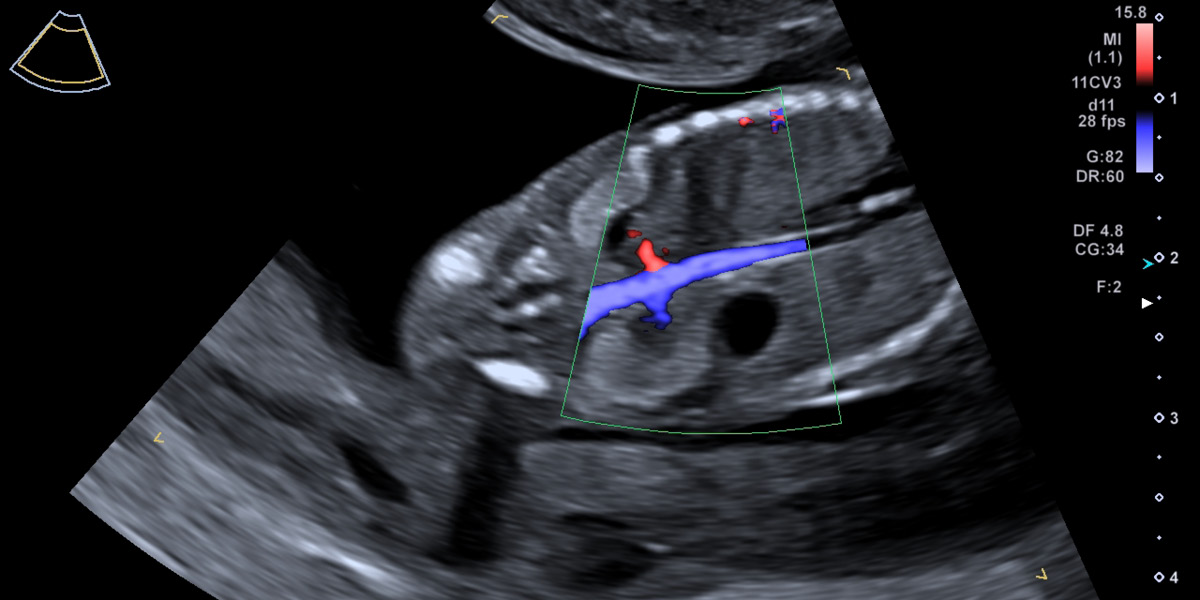

Mit der Nabelschnur fließt der Sauerstoff vom Mutterkuchen direkt ins kindliche Herz. Das Blutflussmuster zeigt einen normalen Fluss, so ist die Wahrscheinlichkeit für Herzfehler und die Trisomie 21 gering.